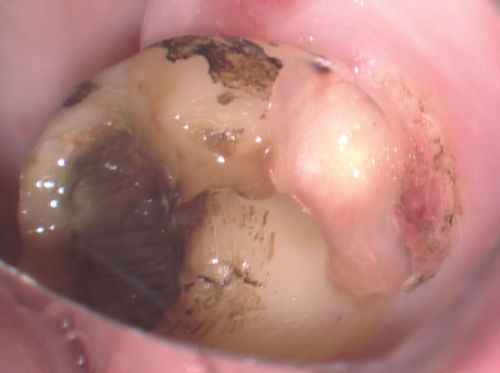

6番のインレイを除去してむし歯を削り取ると露髄しました。写真は冠部歯髄を除去したところ。出血します。つまり健康だと思われる歯髄が露出しています。死んだ歯髄は出血しません。